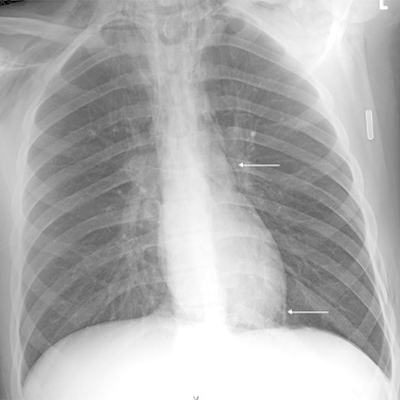

Click on an image below to view more info.